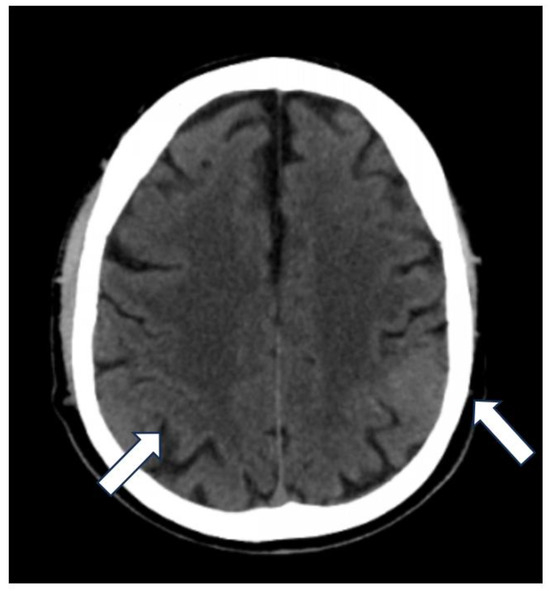

A 60-year-old Caucasian male presented with a secondary generalized focal motor seizure that caused post-ictal right hyposthenia, which resolved after 2 days. Neurological examination showed a slight leveling of the left lower limb during the Mingazzini maneuver, hyperelicitable osteotendinous reflexes in the four limbs with anisoreflexia left > right, pathological Babinski’s sign on the right, and hypopallesthesia of the lower limbs prevalent on the right with a cranio-caudal gradient. The patient had suffered from Waldenstrom macroglobulinemia 6 years before, but he recovered after treatment with Rituximab and Bendamustine. The patient did not have a history of epilepsy or any recent history of fever, vaccine, upper respiratory tract infection, abdominal symptoms, trauma, or travel. He suffered from psoriatic arthritis in treatment while taking Apremilast (300 mg × 2/day). At the time of presentation, the routine blood tests were unremarkable except for a slight increase in erythrocyte sedimentation rate (21 mm/h), lymphocytopenia (0.9 × 102/μL), and thrombocytopenia (127 × 103 μL). An unenhanced brain CT scan at the clinical onset revealed faint hyperdensity in some left parietal subarachnoid spaces (SHSs), which replaced the physiological hypodensity of the liquor (Figure 1). Patients underwent MRI scan after 5 days that revealed pathological signal and leptomeningeal enhancement on both left and right parietal SHSs without diffusion restriction (Figure 2). Further MRI examination performed one week later was negative for spinal cord and radicular/cauda equina alterations (Figure 3) but confirmed the stability of leptomeningeal findings. Leptomeningeal contrast enhancement was suspected for leptomeningitis, post-ictal hyperemia, and metastasis. After 20 days, the patient also underwent a total body CT scan to exclude any primary malignancies. Peripheral blood tumor marker (CEA, aFP, CA19-9, CA125, TPA, PSA, NSE, CYFRA), infective (HSV, HZV, JVC, EBV), and autoimmunity (anti-dsDNA, anti-RNP, anti-Sm) tests were negative. More than one month after the onset, cerebrospinal fluid (CSF) analysis documented the presence of monoclonal bands (light chain k, IgM) with elevated IgM index (0.45) calculated by [CSF IgM (mg/L)/serum IgM (g/L)]/[CSF albumin (mg/L)/serum albumin (g/L)] that is [1.89 (mg/L)/7.13 (g/L)]/[28.3 (mg/L)/48 (g/L)]. CSF flow cytometry revealed 2527 cells and 850 lymphocytes (33.64%). Among CSF lymphocytes, 87% of them were CD3+ CD5 +, while only 8% of them were CD19+ CD20+. The CSF tests did not reveal the presence of infectious meningitis (HSV1, HSV1, EBV, Adenovirus, Enterovirus, Parechovirus). The polymerase chain reaction test was negative for the L265P mutation in the MYD88 gene in both CSF and blood samples. CSF and MRI findings, along with the history of WM, were used to suggest the diagnosis of BNS within 2 months of the clinical onset (diagnostic timeline, Scheme 1). Therefore, brain tissue biopsy was not performed. A treatment with ibrutinib (140 mg three times daily) was initiated for the patient and is still receiving it. During a 1-year follow-up, there have been no new neurological signs or symptoms. The latest brain MRI showed a new subcortical left parietal lesion (18 mm) that was suspected to be caused by neoplastic cells infiltrating white matter vessels. Despite this, the spectroscopy map did not reveal any abnormal metabolic peaks in the lesion (Figure 4). The patient accepted the diagnosis and started and followed the therapy correctly. Despite his thrombocytopenia worsening, he tolerated the treatment well.

Figure 1. The unenhanced CT axial image reveals on the left side the disappearance of the physiological hypodensity of the subarachnoid spaces in parietal region where, instead, there is a slight hyperdensity (arrows).